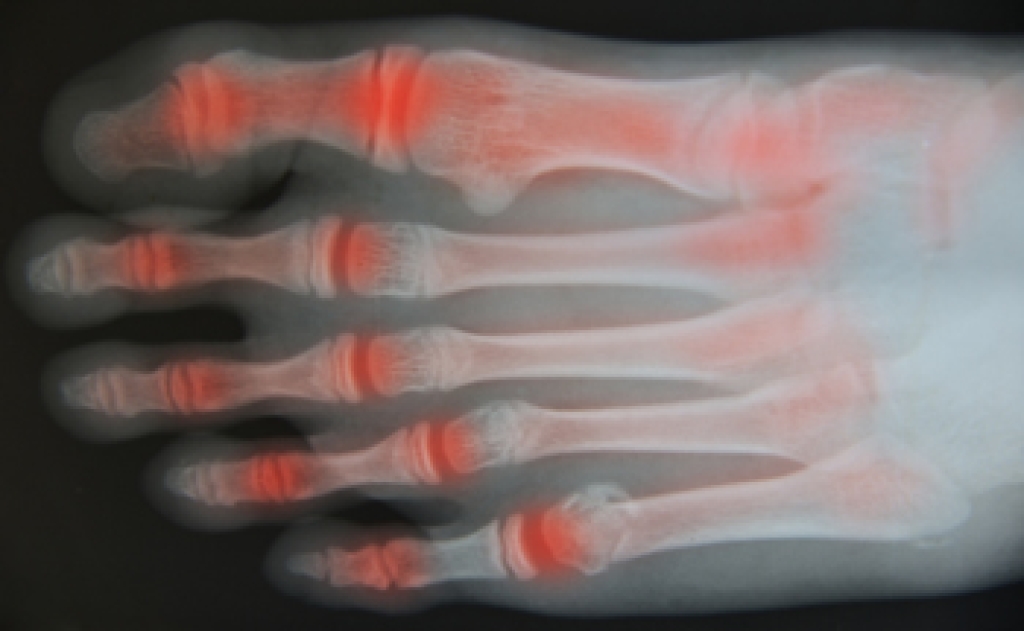

Foot arthritis causes inflammation and damage to the joints of the foot, leading to pain, stiffness, and reduced mobility. Osteoarthritis results from wear and tear of the joint cartilage over time. Rheumatoid arthritis is an autoimmune condition where the body attacks its own joints, causing swelling and deformity. Additionally, post-traumatic arthritis develops after an injury or fracture, while gout occurs when uric acid crystals accumulate in the joint, causing sudden and severe pain. A podiatrist can diagnose the specific type of arthritis, recommend treatments such as custom orthotics or medication, and provide guidance to improve mobility. If you have symptoms of arthritis in your feet, it is suggested that you are under the care of a podiatrist.

Arthritis is a term that is commonly used to describe joint pain. The condition itself can occur to anyone of any age, race, or gender, and there are over 100 types of it. Nevertheless, arthritis is more commonly found in women compared to men, and it is also more prevalent in those who are overweight. The causes of arthritis vary depending on which type of arthritis you have. Osteoarthritis for example, is often caused by injury, while rheumatoid arthritis is caused by a misdirected immune system.

Arthritic symptoms range in severity, and they may come and go. Some symptoms stay the same for several years but could potentially get worse with time. Severe cases of arthritis can prevent its sufferers from performing daily activities and make walking difficult.